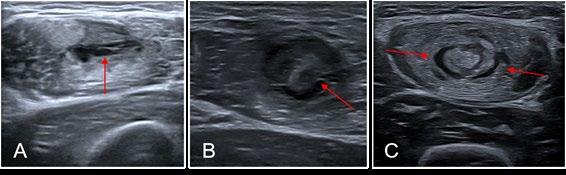

Figure 1: Reproduced from Entwisle et al. The anterolateral epimyseal surface of the long head (L) condenses to form the proximal portion of the distal musculotendinous junction. The opposing epimyseal condensations at the anterolateral aspect of the long head (L, large arrow) and the posterolateral aspect of the short head (S, small arrow) form the midportion of the distal musculotendinous junction that appears T-Shaped.

T-Junction Injuries

It is not just intramuscular tendon injuries that have particularly high re-injury rates. Consideration needs to be given also to the distal hamstring, which may have its own characteristics. Kenneally-Dabrowski, et al. 12 noted that amongst a group of professional rugby players, distal hamstring injuries were the injuries typically classified as more severe. Entwisle, et al. 13 was the first to describe what is now known as the T-Junction of the distal hamstring. This is the confluence of the epimyseal surfaces of the biceps femoris long head and short head (Figure 1). These authors report re-injury rates for this sub-type of hamstring injury at 70% for the higher grade injuries, which must be the highest reported re-injury rate for any muscle injury. 13 Similarly, Kayani, et al. 14 noted 55% recurrence rates from conservatively managed injuries to this area. Shamji, et al. 7 in their group of professional footballers at Aston Villa found that most of the re-injuries they had, were indeed in the region of the T-Junction.

These injuries are difficult to diagnose without imaging. It is characteristic of T-Junction injuries that they present well early (perhaps due to limitations in clinical assessment in appropriately straining the T-Junction) and it is only when they progress through rehabilitation and reinjure that the severity becomes clear.

Thus, it is advocated that any acute distal hamstring injury should be treated with suspicion. The T-Junction confluence can be palpated in prone, located at the most distal component of long head where the short head condenses - usually 5cm (range 1.5-10) proximal to the knee joint space. A distal to proximal approach to palpation is advocated, to reach the thickening where the common insertion broadens to form two muscles, with short head the more lateral. While this is often a tender area even in an uninjured athlete, a side-to-side comparison should be a part of every hamstring assessment. In more severe injuries, an experienced practitioner may detect a defect.

MRI is the probable imaging type of choice to confirm diagnosis, although dynamic ultrasound is also useful. Synchronous movement of the short and long heads during an isometric prone curl can be assessed and monitored as either a prognostic or progress indicator, though a reliable and valid protocol has yet to be described.